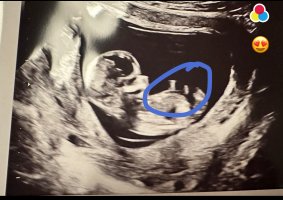

trodde kanskje det var noe ) se hvor jeg har satt ring på bildet hihi

? Er 13+1 her